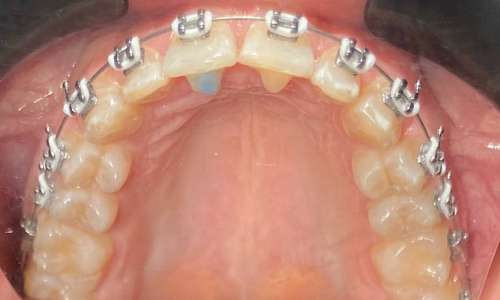

Со временем врач уменьшая высоту накладок, чтобы зубы начинали смыкаться в новом положении, постепенно входя в контакты. После лечения врач убирает накладки.

Передние накладки (bite turbos) – используются при низкой высоте прикуса, глубоком резцовом перекрытии, заднем положении нижней челюсти.